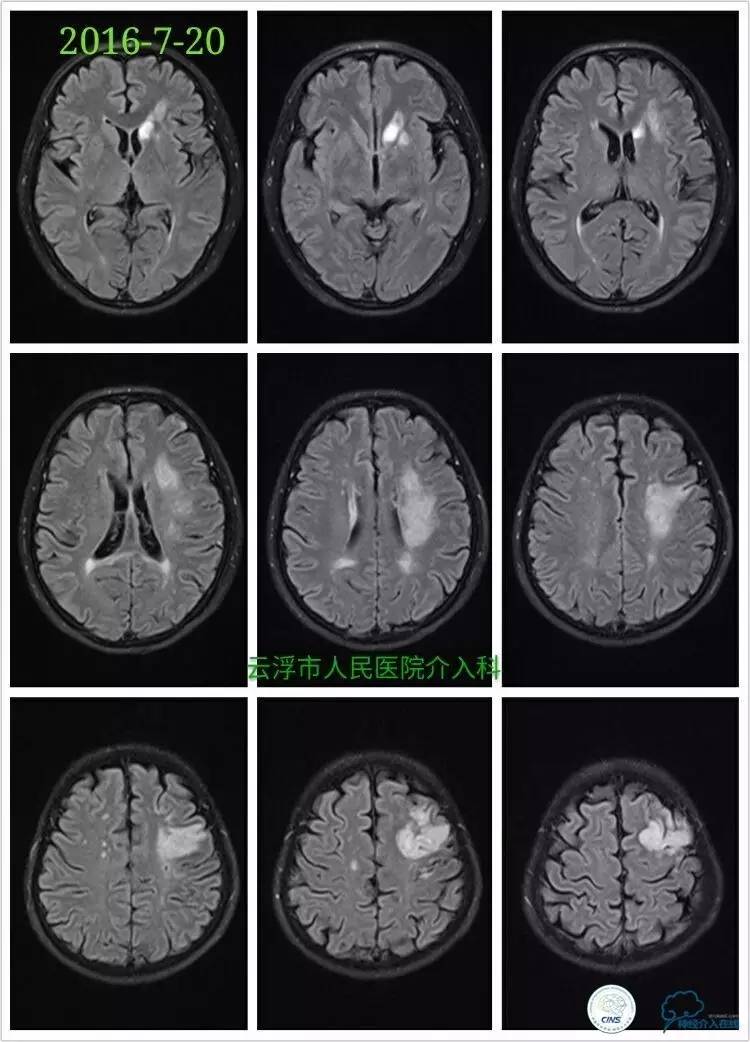

》2016-7-20

颅脑MRA检查:左侧额颞叶、基底节区、放射冠区急性脑梗塞,左侧颈内动脉颅内段重度狭窄。